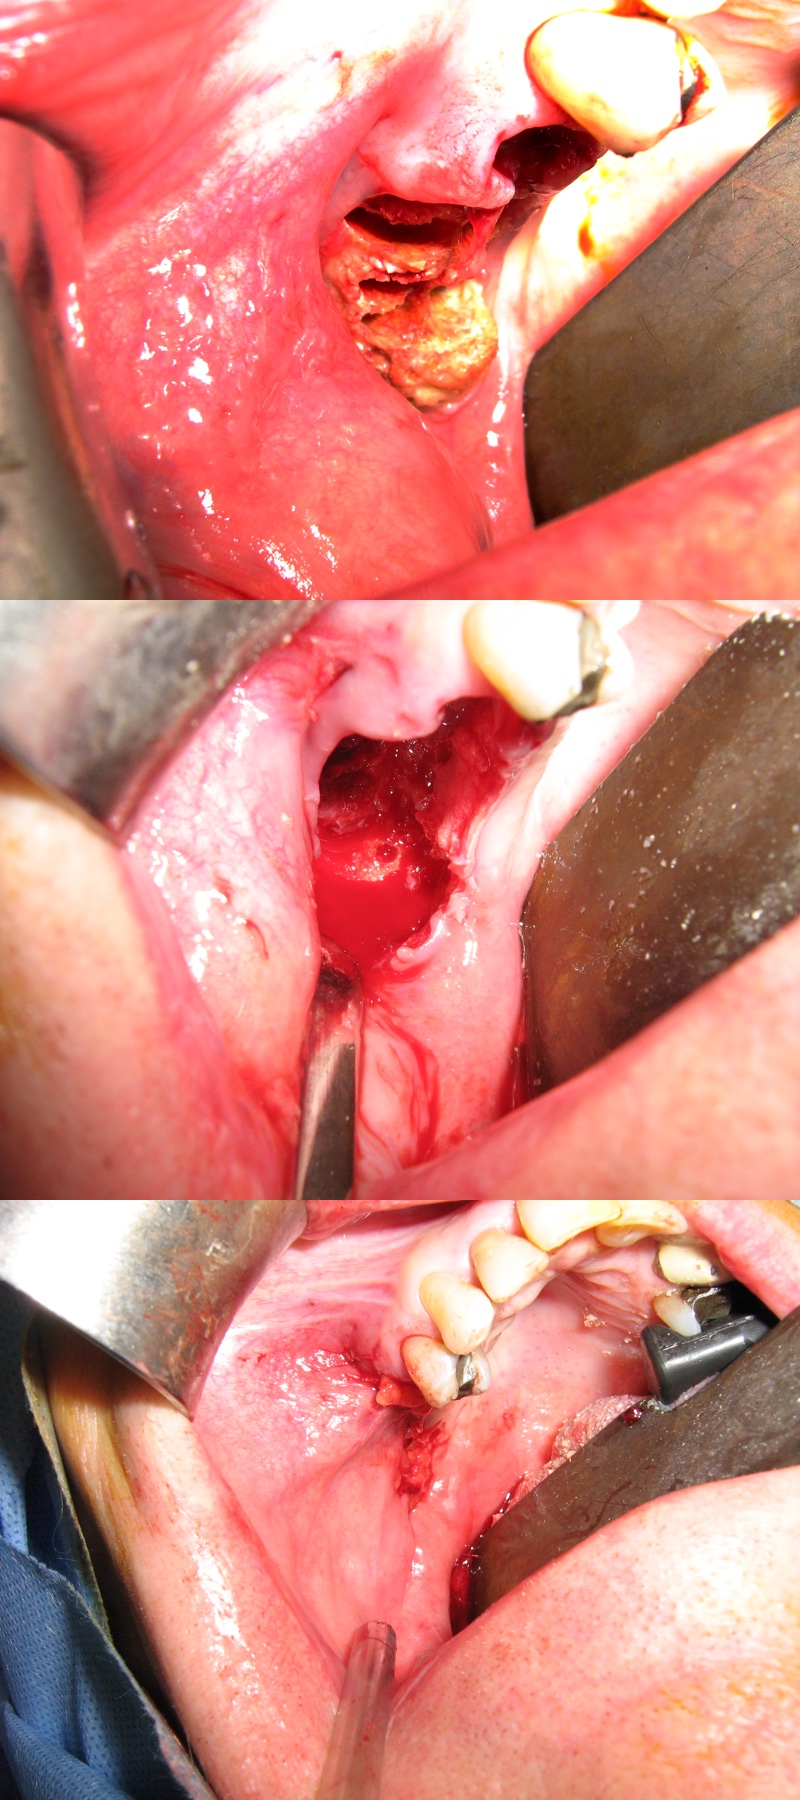

More extensive forms of ONJ require more extensive surgical strategies. These include removal of all necrotic bone (sequestrectomy), smoothing of bone edges, decortication (Figure 2). In some such cases, primary wound closure may still be possible. With increasing defects, it is more likely that vascularised local soft tissue will be needed to provide a local flap for an effective seal. Other possibilities for wound closure are regional or free soft-tissue flaps.

Figure 2: Débridement followed by coverage with local vascularised tissue.